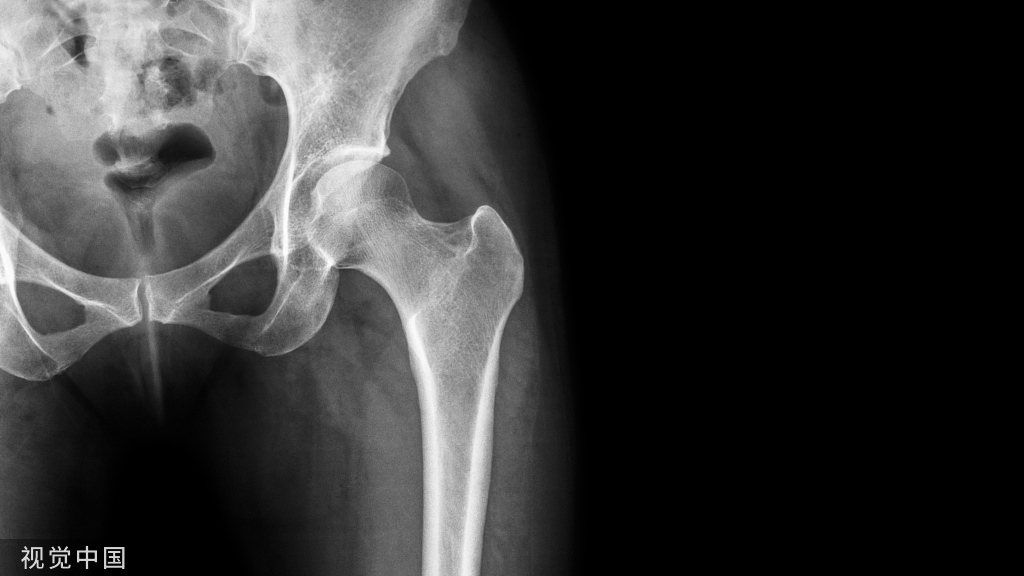

1.骨不连分类

(1)肥大性骨不连,骨端血运丰富,固定不良。

(2)营养不良性骨不连,骨端象牙白或淡黄色,无骨膜。

(3)萎缩性骨不连,骨端萎缩、骨质疏松、断端呈鼠尾状改变,无任何骨痂形成。

(4)感染性骨不连,骨折端呈蚀样改变,并夹杂骨感染表现,即骨溶解、死骨存留、异常的局限性密度增高。

(5)假关节性骨不连,骨端间形成封闭的假性关节囊。

(6)骨缺损性骨不连,缺少全周径的2cm以上,多因创伤、手术、肿瘤切除或自身代谢性原因。